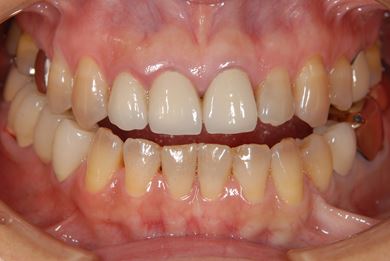

治療前

• 治療前